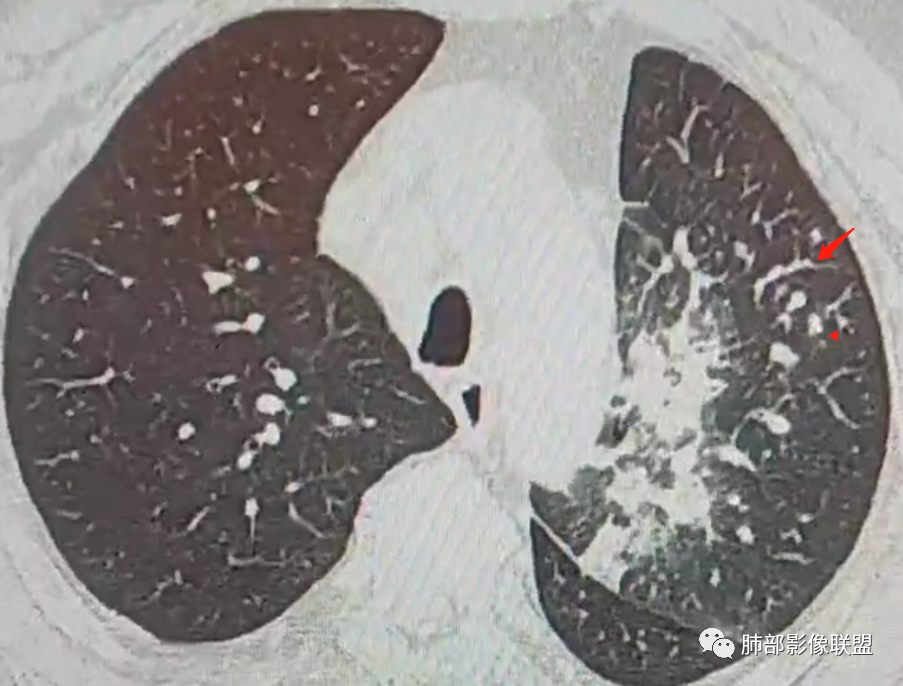

南边:这些是中轴间质增厚?树芽征?

Coke with ice:潘老师,这里是小叶间隔吧?串珠样的。

南边:是的。

南边:尖后段弥漫小叶间隔,中轴间质增厚,部分有结节感,大家考虑啥。

Coke with ice:我觉得是典型的癌淋,较大范围的,比如叶分布,甚至是整个单侧肺,单侧的肺小叶间隔增厚,极大概率是癌淋,另外一个疾病谱就是负压性肺水肿。

Coke with ice:这里有点像原发。隆突下也有大淋巴结。